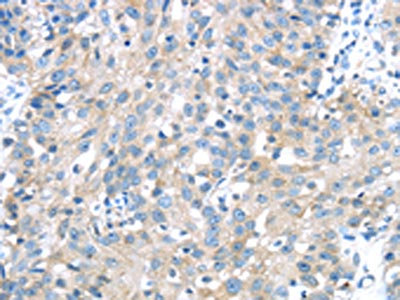

The image on the left is immunohistochemistry of paraffin-embedded Human breast cancer tissue using CSB-PA824414(IGFBP3 Antibody) at dilution 1/40, on the right is treated with synthetic peptide. (Original magnification: ×200)